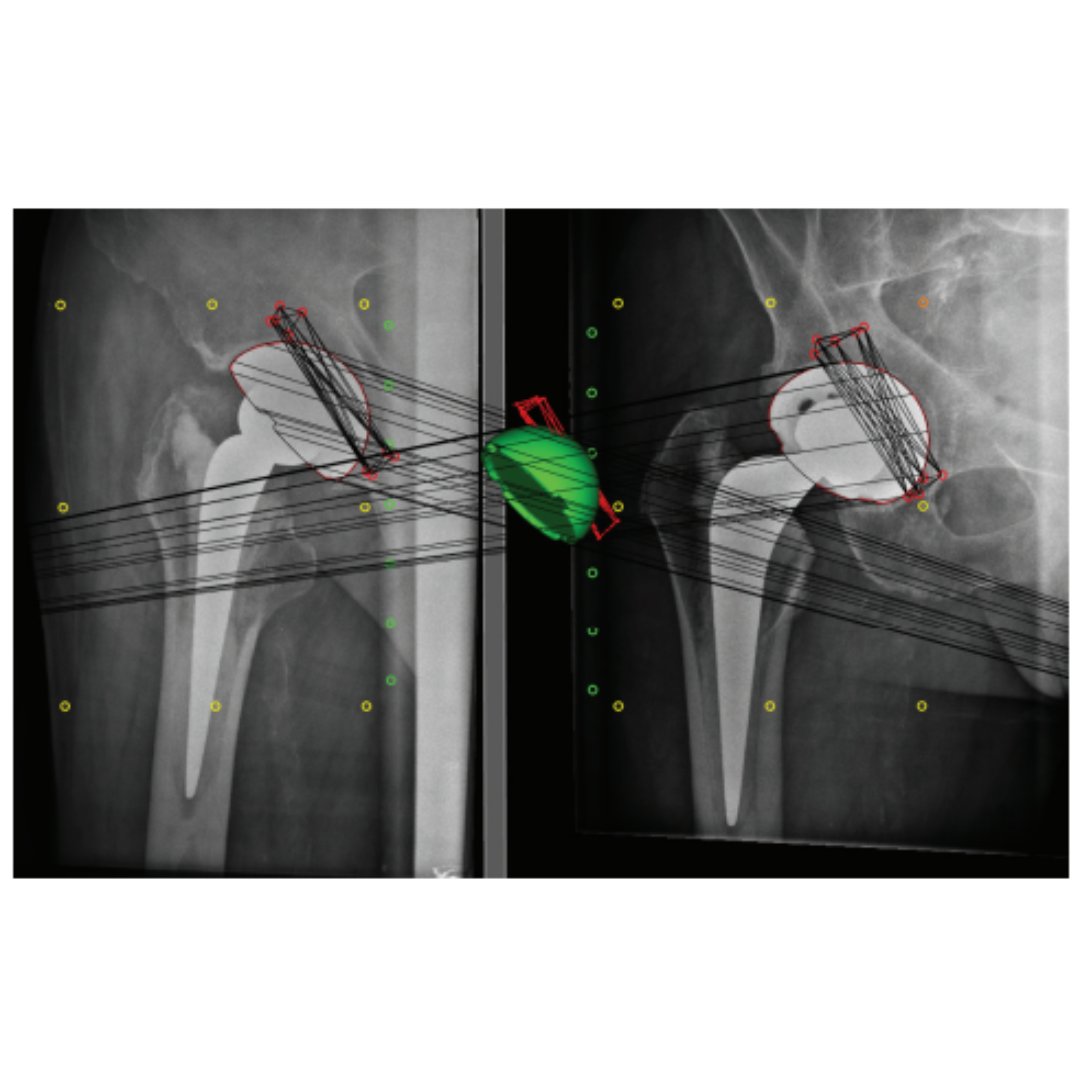

Does acetabular retroversion represent a structural anatomical abnormality of the pelvis, or is it a functional phenomenon of pelvic positioning in the sagittal plane? #Hip #Radiograph #BJJ @ortho_pods ow.ly/1JGA50QvPCF

The Trident II clusterhole hydroxyapatite (HA) shell has comparable migration with its predecessor, the Trident hemispherical HA cluster shell, suggesting a similar risk of long-term aseptic loosening. #BJJ #Arthroplasty #Radiograph ow.ly/27Yj50QvRmx